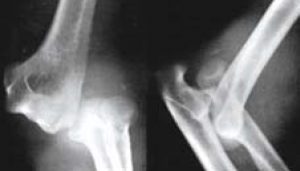

Bei einer Ellenbogenverrenkung (Luxation) (Abb. 60) kann es zu erheblichen Verletzungen der Knochen und der Weichteile kommen. Die unkomplizierte Luxation, die schnell einer Einrenkung (Reposition) zugeführt wird, heilt in den meisten Fällen auch unter konservativen Maßnahmen aus. Liegen jedoch so erhebliche Schädigungen vor, dass eine sofortige Instabilität verbleibt oder der Weichteilschaden zu groß ist, wird die operative Stabilisierung notwendig.

Auch nach konservativer Behandlung kann es zu einer verbleibenden Instabilität kommen, die sich darin äußern kann, dass der Ellenbogen tatsächlich wieder auskugelt oder bei bestimmten Bewegungen und Belastungen sich nicht mehr sicher anfühlt, weil diese zu einer Subluxation führen und der Arm „wegknickt“ oder schmerzt. Führt die Luxation gar zu knöchernen Verletzungen, ist in der Regel eine Operation unumgänglich.